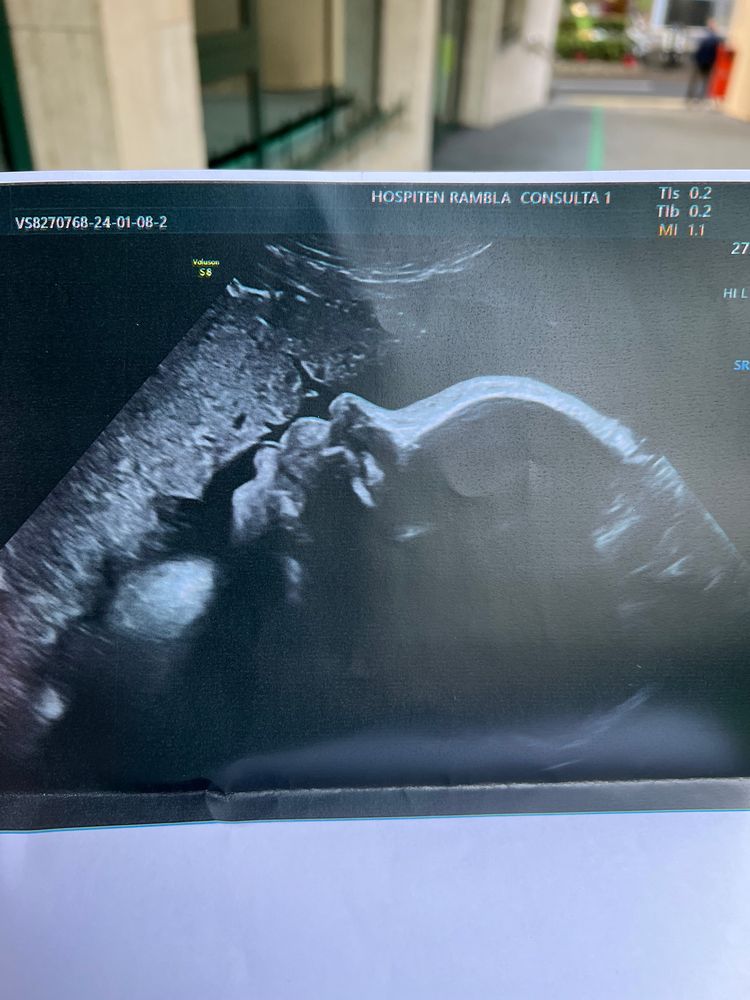

38 недель 5-ой беременности

Вчера на приёме врач сделал узи (делают каждый прием), с малышкой все хорошо. Весит примерно 3 кг, моя прибавка - 9 кг. На узи дочка высовывала язык 🥰🥰🥰

после приёма отправили на первое ктг. Все хорошо. Зафиксировались 2 схватки. Чувствовала их.